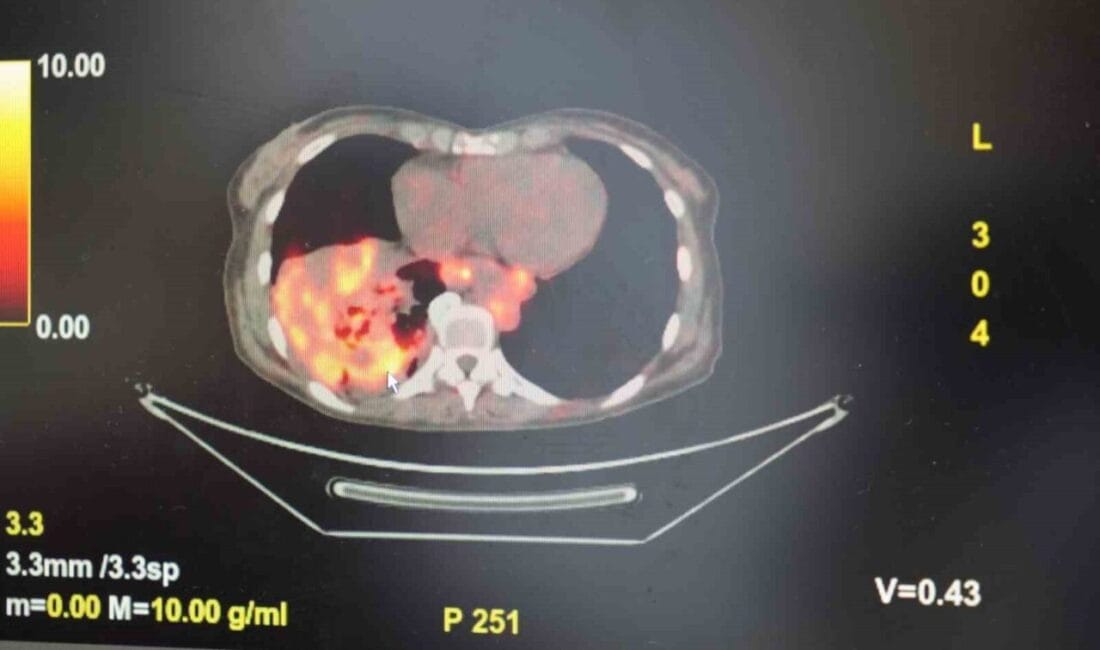

’Sigarasız akciğer kanseri’ vakalarında dikkat çeken artış

Göğüs Hastalıkları Uzmanı Prof. Dr. Şevket Özkaya, son yıllarda sigara kullanmayan bireylerde de akciğer kanseri vakalarının dikkat çeken bir oranda arttığını belirterek, özellikle kadınlarda görülen adenokarsinom tipi akciğer kanserinin artış gösterdiğine dikkat çekti. Bu konuda yapılan son araştırmalara değinen Özkaya, akciğer kanseri teşhislerinin yaklaşık yüzde 20’sinin hiç sigara içmemiş bireylerde konduğunu söyledi.

Dünyanın en prestijli tıp dergilerinden yayımlanan bir araştırma üzerinde açıklama yapan Prof. Dr. Şevket Özkaya, araştırmaya göre, sigara içmeyenlerde en sık görülen tür olan akciğer adenokarsinomu, kadınlarda akciğer kanserlerinin yaklaşık yüzde 60’ını oluşturduğunu söyledi. Prof. Dr. Özkaya, sigara dışındaki risk faktörlerinin başında radon gazının geldiğine dikkat çekerek, “Radon gazı, evlerimizde farkında olmadan soluduğumuz, renksiz, kokusuz, tatsız ve radyoaktif bir gazdır. Müsaade edilen değerlerin üzerinde solunduğunda akciğer kanseri riskini artırıyor. Radon gazı özellikle taş, toprak ve çimento gibi yapı malzemelerinde doğal olarak bulunuyor. Bu maddelerden ortama sürekli yayılan gaz, solunum yoluyla akciğerlere ulaşıyor” ifadelerini kullandı.